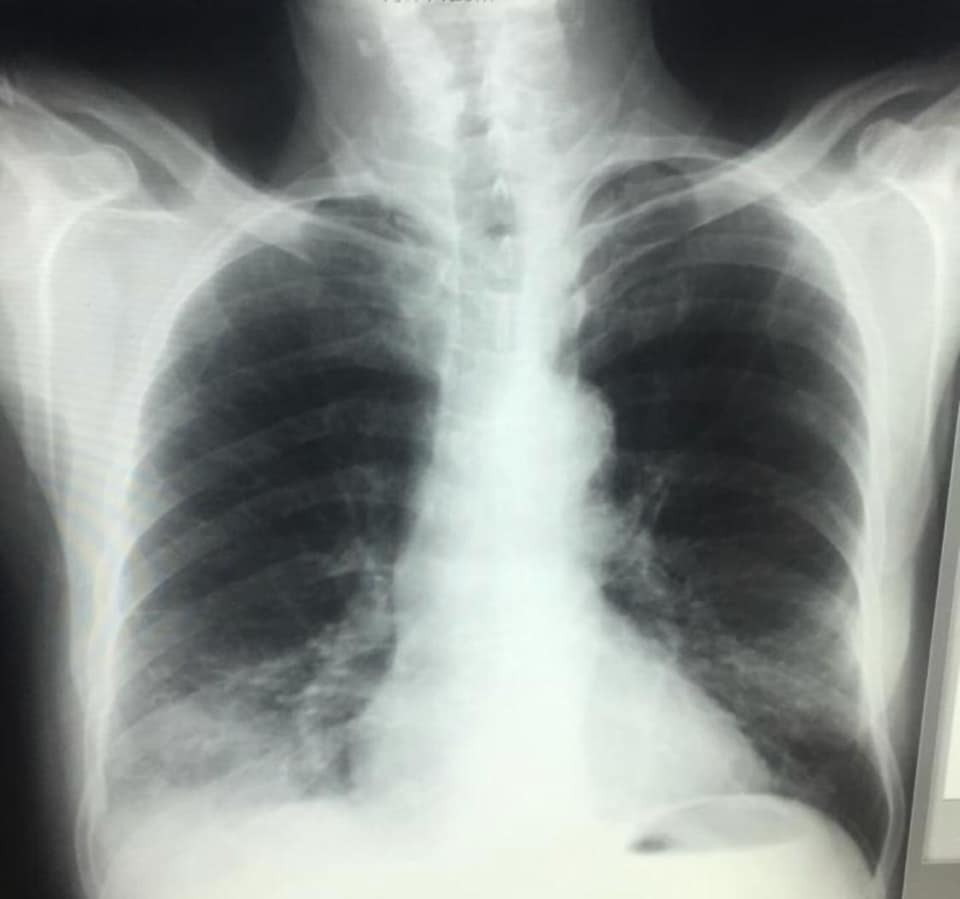

IMAZHET E JANARIT QË FLASIN PËR PREZENCËN E COVID-19 NË SHQIPËRI QË NË KËTË PERIUDHË

Sot, falë mikut dhe kolegut tim të nderuar Dr. Renato Osmani…, imazhëristit që ishte i pari, që javën e parë pas zbulimit të të ashtuquajturit rast 0, identifikoi fizionominë dhe identitetin imazhërik pulmonar të COVID-19… dhe potencën e ekzaminimit CT ndër ekzaminimet e skemës bazë për diagnostikim dhe përcaktim prognose…, mu ofruan imazhe të pakundërshtueshme të prezencës së COVID-19 në datat 15 – 20 janar, në disa raste në Infektiv…!!!

Faleminderit Dr. Renato…, jo vetëm për menaxhimin pa panik, por me vigjilencë të situatës së karantinës, nëpërmjet centarlizimit dhe koordinimit nacional imazhërik për suspektim sa më të hershëm të sëmundjes dhe prevenimin e kaosit, që mund të kish shkaktuar strategjia e gabuar e numrit 127…, por edhe për ndihmën që po jep për Komitetin Teknik për konfuzionin në pritjen e pikut epidemiologjik…!!! Po ju ofroj pamjet imazhërike të pesë rasteve, duke ju kujtuar që janë pronë intelektuale e Dr. Renato Osmani dhe i publikoj me aprovimin e tij, duke mbrojtur të drejtën e tij të aitorit…!!!